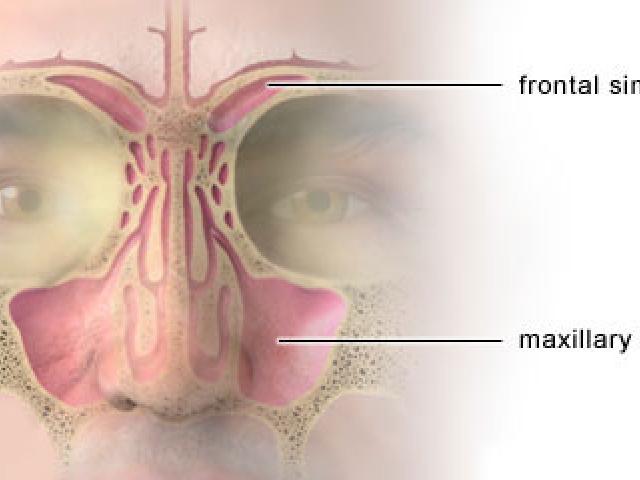

El dolor de cabeza es, quizás, uno de los malestares más comunes a los que se puede enfrentar una persona. La mayoría lo experimenta más de una vez a lo largo de su vida, sobre todo, porque está vinculado a enfermedades comunes como la gripe, el resfriado o la sinusitis.